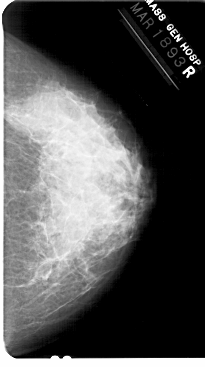

A_1361_1.RIGHT_MLO

RIGHT_CC LINES 5491 PIXELS_PER_LINE 3061 BITS_PER_PIXEL 12 RESOLUTION 43.5 NON_OVERLAY